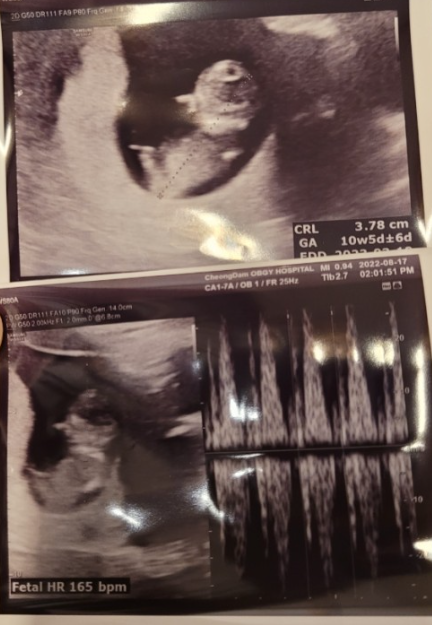

■임신기록 #12■ 임신 12주차 기록 (청담마리산부인과 1차 기형아 검사 / 입체 초음파 / 정말 초음파 / 각도법?)

이제부터 이론상 주수 기록은 그만.. 내 기록만 할 거다.. 왜냐하면.... 너무 길어!!! 옮겨 적기 힘들어유....

■임신기록 #10■ 임신 10주차 기록(입덧약 복용 및 효과 / 양수량과 수분섭취량의 상관관계 / 임산부 미용실 / 하이베베 구매 / 자궁통증 등10주차 증상)_슬키로운

이론상 10주 차 증상은 맨 아래에 기재해 두었다. 먼저, 나의 10주 차 기록부터 시작! ❤ 임신 10주 차 ✔ ...